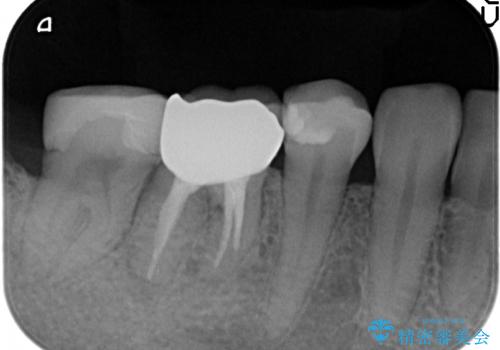

- たまに疼くことがあると他院を受診したところ抜歯を勧められたが、歯を残せないものかと当院にいらっしゃった方の症例です。

診査の結果抜歯の必要性はなさそうだったため再根管治療を行い、その後オールセラミッククラウンによる補綴を行いました。

今回用いたオールセラミッククラウンはジルコニアフレームという白い素材の上にセラミックを盛っているため、審美性が非常に高いのが特徴です。

また、ジルコニアは人工ダイヤモンドの材料にも使われているほど高い強度を持っており、そのためオールセラミッククラウンは審美性だけでなく、奥歯やブリッジの補綴も可能とするクラウンです。